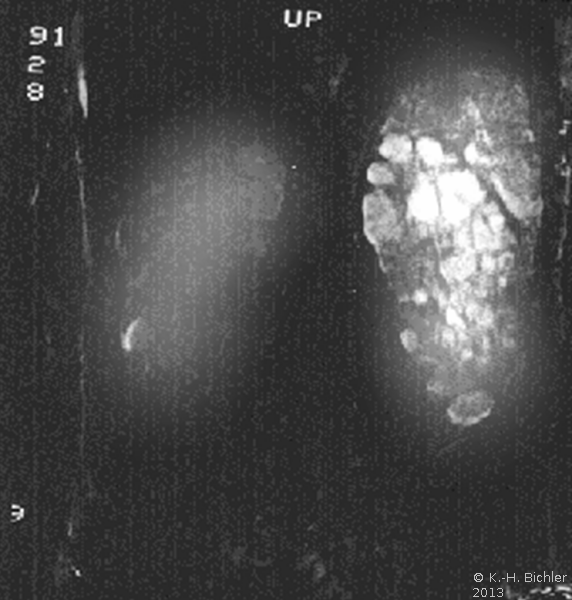

Die Diagnose wird mittels Anamnese (zystische Nierenerkrankungen in der Familie), RR-Messung, Labor (Kreatinin) mit genetischer Untersuchung, Sonographie, Computertomographie und gegebenfalls Kernspintomographie gestellt (Abbildung 4).